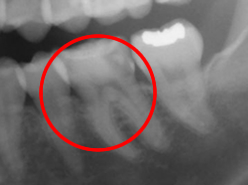

下の写真は奥歯の歯と歯の間の虫歯が大きく神経まで達していたケースですが、ラバーダムがなければ、唾液や血液で象牙質また神経(歯髄)が汚染されてしまいます。